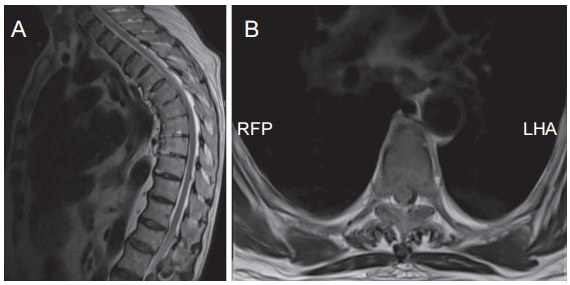

辅助检查:血常规、凝血功能、感染四项等化验结果均未见明显异常,尿常规:葡萄糖 (±),镁离子:0.76 mmol/L,血糖:8.16 mmol/L。完善胸椎 X 线片(见图2)、胸椎磁共振检查(见图3)。

图3 胸椎 MRI

(A) 胸椎 MRI 矢状位;(B) 胸椎 MRI 水平位